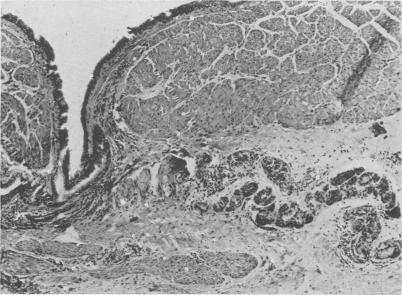

Bronchiogenic Cysts of the Mediastinum.